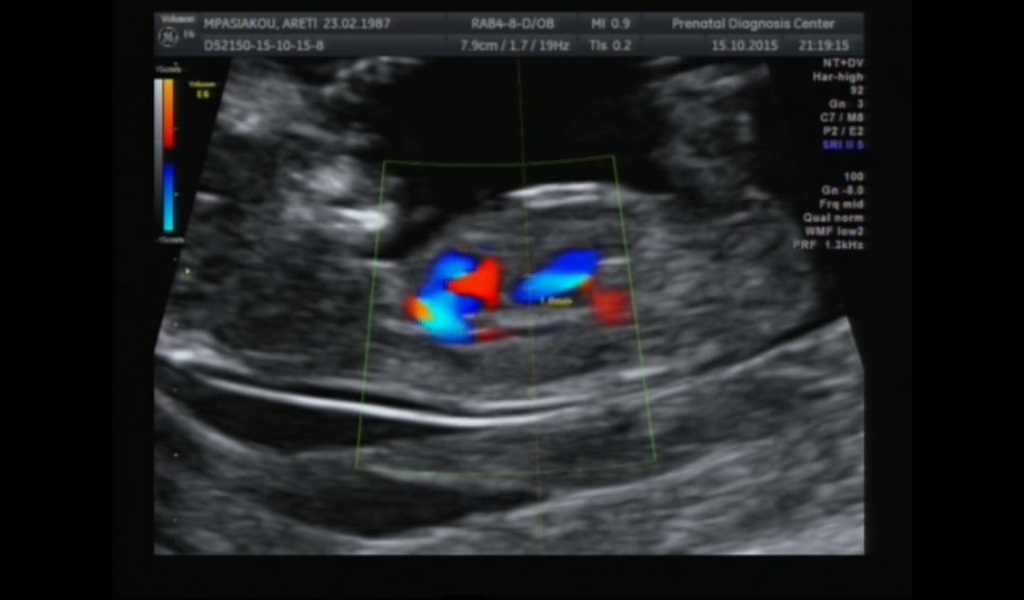

This ultrasound is on the 12th week. Can you guess?

Quote: Originally Posted by Boyzmommy No clue Attachment 27857 NT